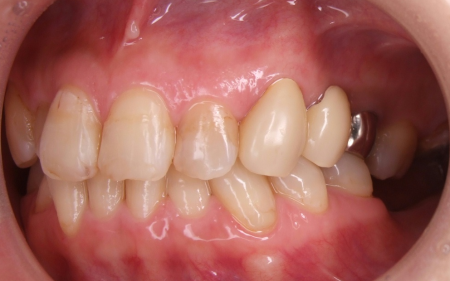

下の奥歯5本(右第2小臼歯/5番、左右第1大臼歯/6番、左右第2大臼歯/7番)が欠損したまま長く放置されていたことが原因で、噛み合う歯がなかった左上の奥歯(第1大臼歯)は本来の位置より下に伸びる「挺出(ていしゅつ)」が起き、左下の歯2本(第1小臼歯/4番、第2小臼歯)も内側に倒れたことで、下前歯の叢生が悪化したと考えられます。

さらに左上の歯(第1小臼歯)の欠損部位は両隣の歯2本(犬歯/3番、第2小臼歯)を土台に人工歯を橋渡しにする被せ物「ブリッジ」が装着されており、お口を開けたときに銀歯が目立つことに加えて、歯の色が全体的に黄ばんでいるため見た目が良くない状態でした。

挺出した左上奥歯(第1大臼歯)がこの患者さまにとって最も大きな問題でした。PAというセファロ分析では、この伸び出た左上奥歯によって左右の上顎第一大臼歯結んだ咬合平面が極端に右上がりになっていました (キャント)。このままインプラントの歯をいれてしまうと顎関節症だけでなく、顔が歪んでしまうリスクもあります。しかし、全体的には咬合高径が低下した状態であったため、適切な咬合高径と咬合平面を矯正治療にてバランスよく設定するのは難しいケースでした。咬合治療の進め方としてはまず、最初に適切な咬合高径、咬合平面を決定することが重要になります。これは総入れ歯の治療と同様です(要素A)。